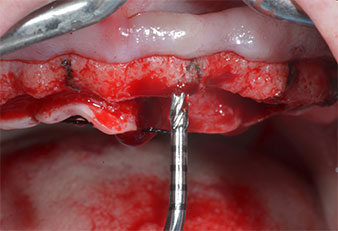

Im vorliegenden Fall wurden die Instrumente Z25P und Z35P wegen des relativ weichen posterioren Knochens nicht verwendet, der problemlos mit dem I3A/I3P bearbeitet werden konnte.

Wegen des relativ harten Knochens (D2) an den Positionen 11 und 21 wurden die 10 mm langen Implantatlager in diesem Bereich abschließend mit einem 4-mm-Spiralbohrer, dem chirurgischen Winkelstück WS-75 L von W&H und dem W&H Implantmed Implantologiemotor in Verbindung mit dem optionalen W&H Osstell ISQ module präpariert. Im Gegensatz dazu wurde der weiche Knochen der Implantatlager im Seitenzahnbereich mit dem Piezomed I3P auf den abschließenden Durchmesser von 3 mm erweitert. Die Implantate wurden dann transgingival eingesetzt, die Einheildauer betrug drei Monate (Abb. 6-10). Die vorhandene Prothese wurde auf vier provisorischen Implantaten abgestützt (Abb. 8).